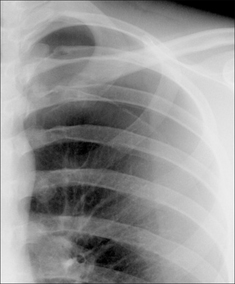

In 95% of patients the CXR is normal. In a few patients the lungs demonstrate hyperinflation—i.e. generalised hyperlucency (increased blackening) with the domes of the diaphragm unusually low.

Figure 29.1 Acute asthma. Normal CXR. This is the most common finding in a patient with an acute asthmatic episode.